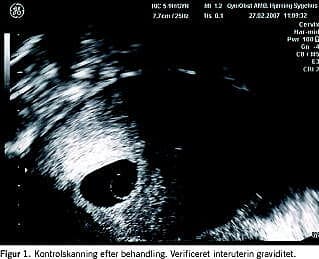

Ved postoperativ kontrol efter tre måneder var patienten generet af mange pletblødninger. Ved en ekstra blødningskontrol efter seks måneder havde patienten haft menostasi i fem uger plus fire dage. Ultralydsskanning viste en mindre cystisk udfyldning lavt på forvæggen, og denne fandtes strukturmæssigt forenelig med tidlig intrauterin graviditet (gestationssæk på 5,9 mm). Der påvises kvantitativ serumchoriongonadotropin (serum-HCG) på 2.745. Ved samme undersøgelse påvistes dysplasia cervisis uteri af moderat grad.

Graviditeter er sjældne efter endometridestruktionsoperationer. Risikoen for graviditet hos i øvrigt fertile kvinder efter endometriablation er meget vanskelig at kalkulere ud fra pu-blicerede data. I disse er ofte inkluderet kvinder, som er blevet steriliseret eller andre, som er infertile af andre årsager såsom intet vita sexualis eller vir steriliseret. En graviditetsrate på 0,7% er formentlig det bedste estimat [3-5] (Figur 1).